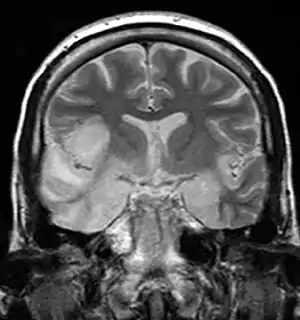

Herpesviral encephalitis and herpesviral meningitis Herpes simplex encephalitis (HSE) is a rare life-threatening condition that is thought to be caused by the transmission of HSV-1 either from the nasal cavity to the brain's temporal lobe or from a peripheral site on the face, along the trigeminal nerve axon, to the brainstem.[19][20][21][22] Despite its low incidence, HSE is the most common sporadic fatal encephalitis worldwide. HSV-2 is the most common cause of Mollaret's meningitis, a type of recurrent viral meningitis.